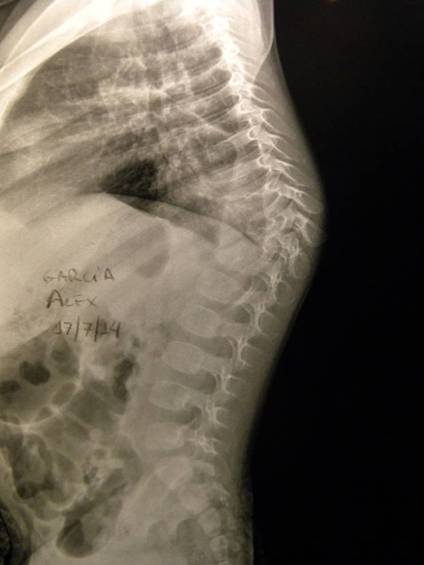

- Figura No 3a

- Figura No 3b

- Figura No 3c

- Figura No 3d

- Figura No 3e

- Figura No 3f

- Figura No 3g

- Figura No 3h

- Figura No 3i

- Figura 3 Texto